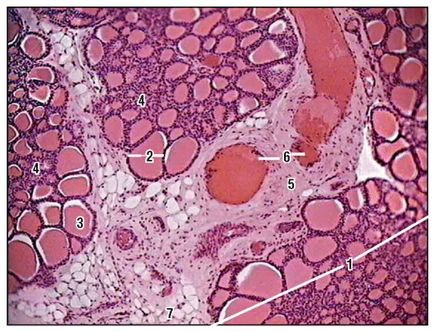

Fig. 168. Glanda tiroidă. Lobule (colorare cu hematoxilină și eozină, creștere mică): 1 - glandă lobulară: 2 - folicul; 3 - coloid în cavitatea foliculului; 4 - epiteliul interfollicular; 5 - țesutul conjunctiv interlobular; 6 - vasele de sânge; 7 - celulele grase